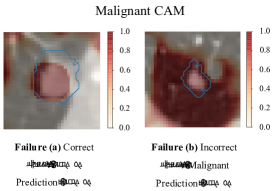

Figure 0.A.1: Two types of failures from a well-trained 3D DenseNet, visualized by CAM techniques. Only malignant CAMs on the central slices are depicted. The blue contours on each plot are manual segmentation of lesions by radiologists. The voxels with higher intensity are more malignant, and those with intensity 0.5absent0.5\leq 0.5 are benign. For failure (a), the model predicts “benign” on a benign nodule correctly. However, this “correct” prediction comes from the prediction apart from lesions on voxels, which means the model uses incorrect evidences. For failure (b), the model outputs “benign” on a malignant nodule incorrectly. Whereas, within the lesion voxels it is indeed predicted as malignant, indicating that the model performance could be boosted further if it uses correct evidences.